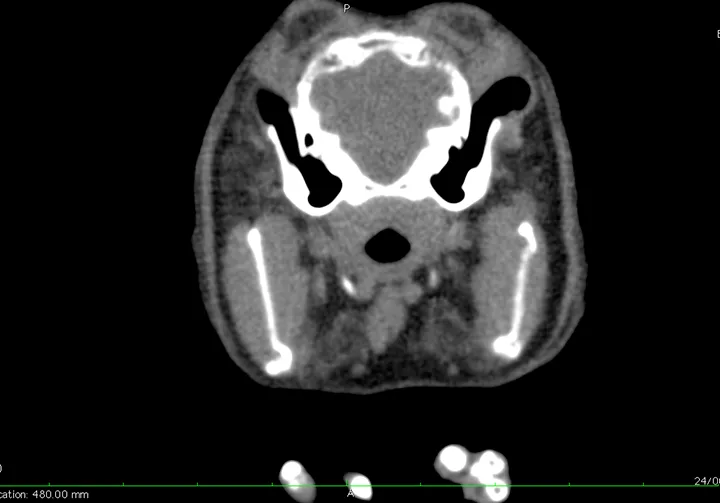

CT was performed after 2 days of supportive care because it is the most sensitive and specific method of diagnosing middle and inner ear disease and ruling out intracranial lesions.5 Results ruled out middle and inner ear disease5 and minimized suspicion for a central brain lesion (Figure 2). MRI is preferable for evaluation of soft tissue structures but was not available.

CT scan showing no evidence of middle or inner ear disease and no central brain lesion. Cerebrovascular accident is not likely visible except with hemorrhage.